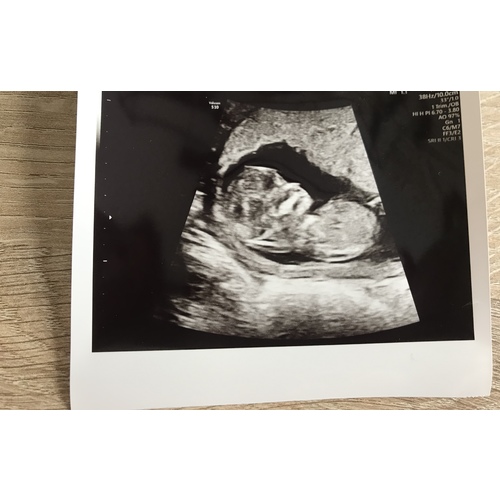

Nou, raad maar raak... haha.

Ben benieuwd wat jullie er in zien.

10w is helaas veel te vroeg voor de Nub theorie